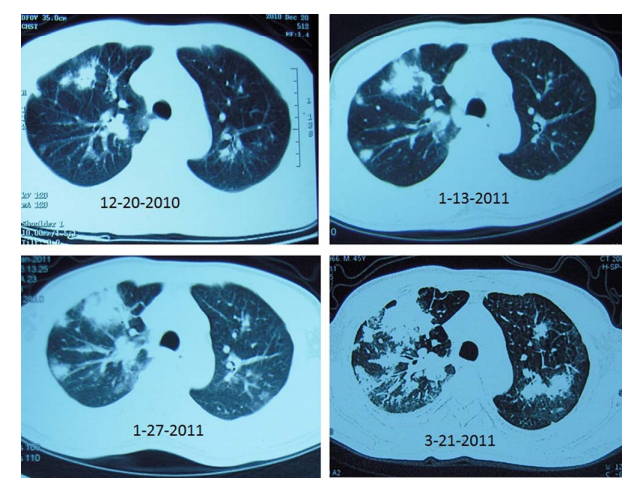

患者的胸部CT表现(图片来自网络)